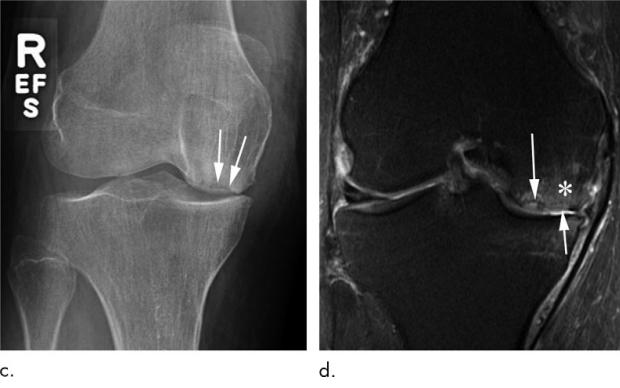

图片c: 11个月后,她因右膝持续疼痛而回来。复查右膝关节前后位片显示股骨内髁关节面塌陷(箭头)。

图片d 冠状位中间加权MRI与图片c显示先前发现的软骨下功能不全性骨折(长箭头)的股骨内髁关节面畸形(短箭头)。此外,还有明显的骨髓水肿(*)。

通过上面的病例我们可以看到,关节内注射激素还是有一定的风险,因此要权衡利弊,下面就对目前对关节内注射激素治疗关节炎的意见与大家分享。